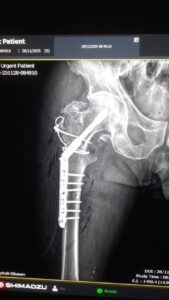

Në Spitalin Rajonal të Elbasanit është realizuar me sukses një ndërhyrje e vështirë ortopedike, që konsistonte në trajtimin e fractura comminutive të regjionit trokanterik të femurit të djathtë. Bëhet fjalë për një thyerje komplekse, e cila kërkon një ndërhyrje të specializuar dhe bashkëpunim të plotë të ekipit mjekësor.

Ky operacion i suksesshëm përbën një tjetër hap të rëndësishëm në rritjen e cilësisë, gamës dhe kompleksitetit të shërbimeve ortopedike në Spitalin Rajonal Elbasan.